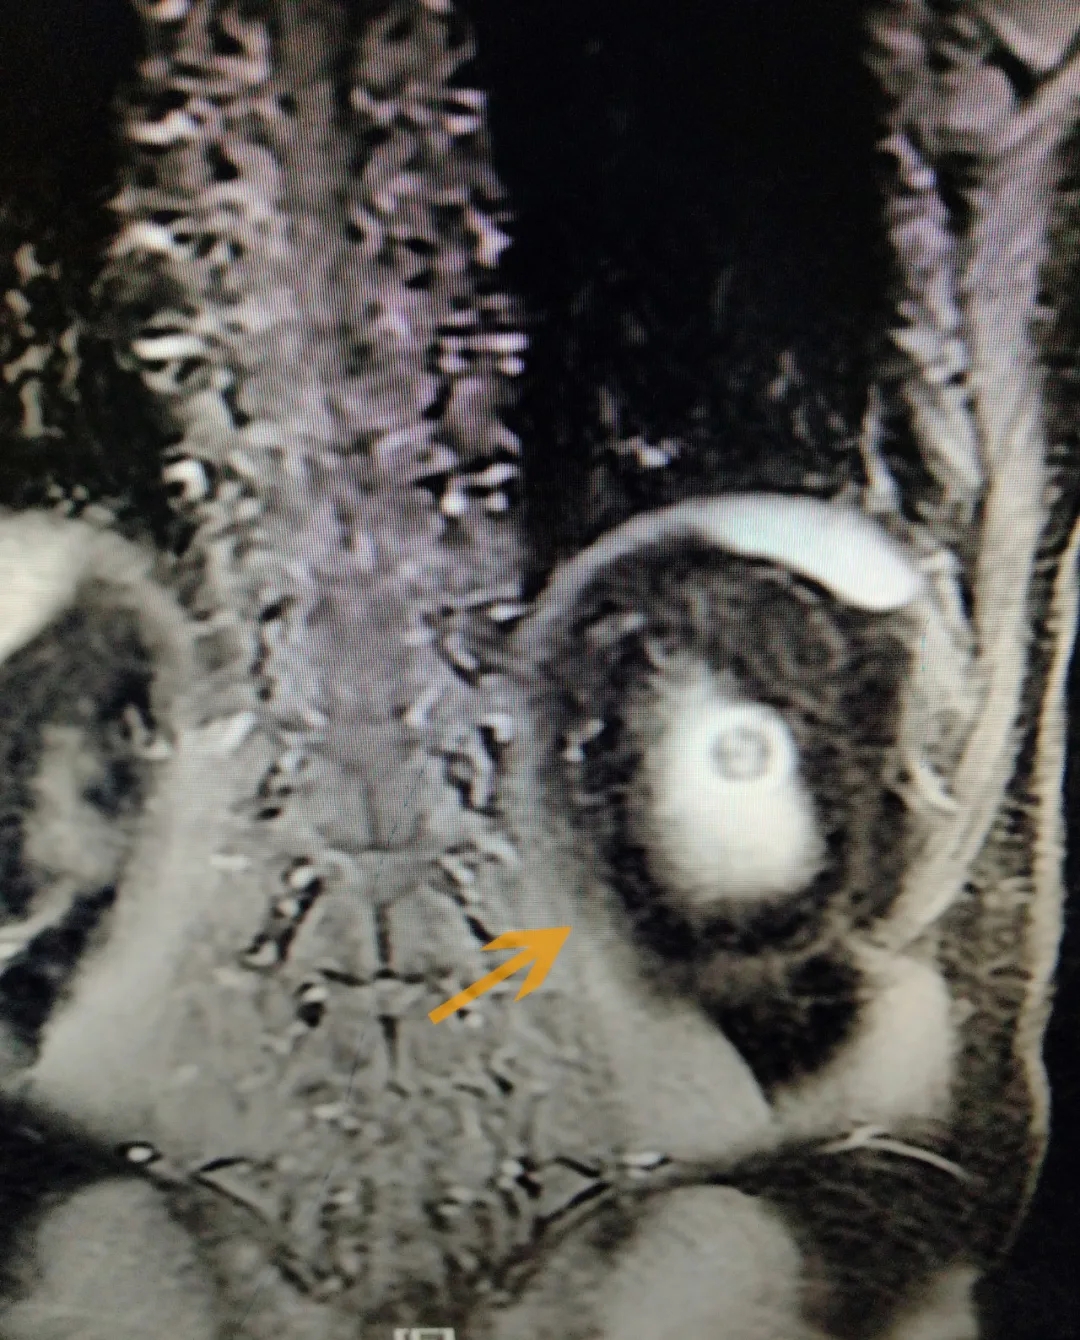

CT检查显示患者左肾有肿瘤